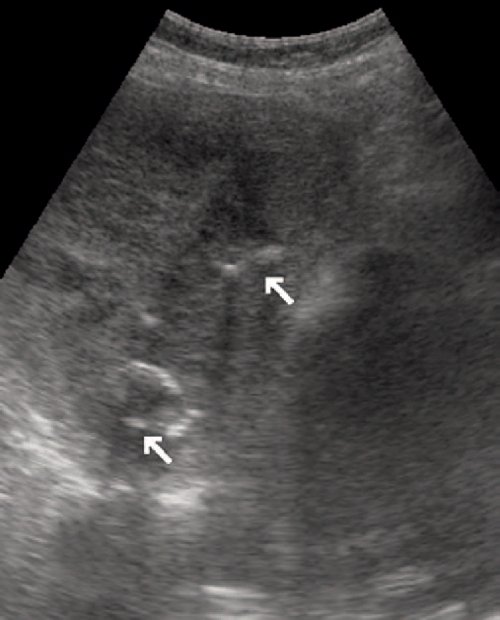

Хирургические процессы при эмболизации гемангиомы на фото

Раздел: Снимки-откровения